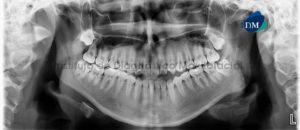

Paciente femenino de 27 años de sexo femenino acude al Instituto de Diagnóstico Maxilofacial para evaluación preoperatoria de cirugía ortognática. A la evaluación de la

Paciente femenino de 19 años de edad, es referido al Instituto de Diagnóstico Maxilofacial – IDM (Sede Miraflores) para exámenes radiográficos para tratamiento ortodóntico y